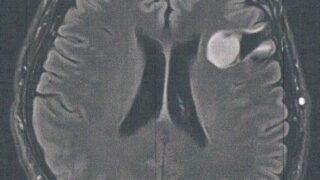

GLIOMA:手術後138ヶ月目の検査

手術から11年が経過した。半年ごとの定期検査です。検査概要びまん性星細胞腫グレード2(悪性転化しやすい腫瘍)MRI検査: 造影剤なし / 造影剤あり造影剤ありの場合:4時間前から絶食し、MRIの1時間前に血液検査を済ませる。診断結果前回のM...